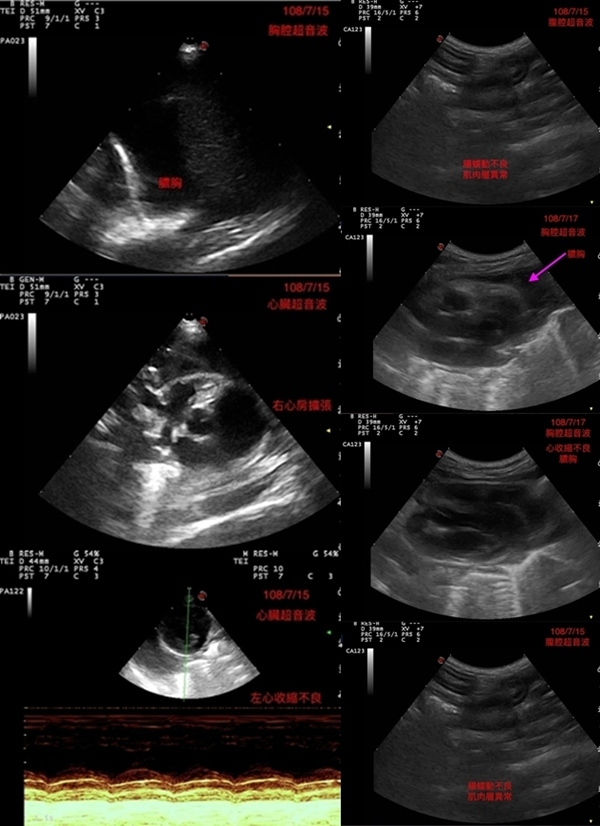

送往醫院檢查與治療, 貓咪送到醫院檢查, 照了腹腔超音波, 有腸蠕動不良, 肌肉層異常. 左心收縮不良, 發現有膿胸敗血與感染, 到院後趕緊幫貓咪處理, 有幫他抽胸水, 還有血檢, 陸續治療照顧貓咪恢復得很好, 後來感染也都控制下來, 但還有一些貧血, 醫生也幫他打造血針和鐵劑.動物近況說明: 在醫院精密的儀器和細心的照顧下, 讓小花從死神的手裡逃出, 出院後安置照顧, 目前有找到願意照顧小花一輩子的人, 感謝大家幫助這隻貓咪的醫療.